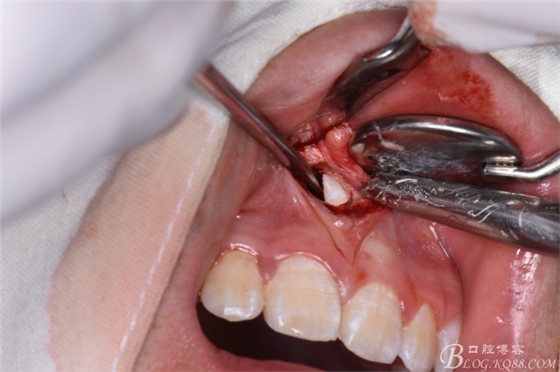

圖22.翻瓣、暴露骨面

圖23.去骨、暴露出鼻底下方的倒置多生牙。